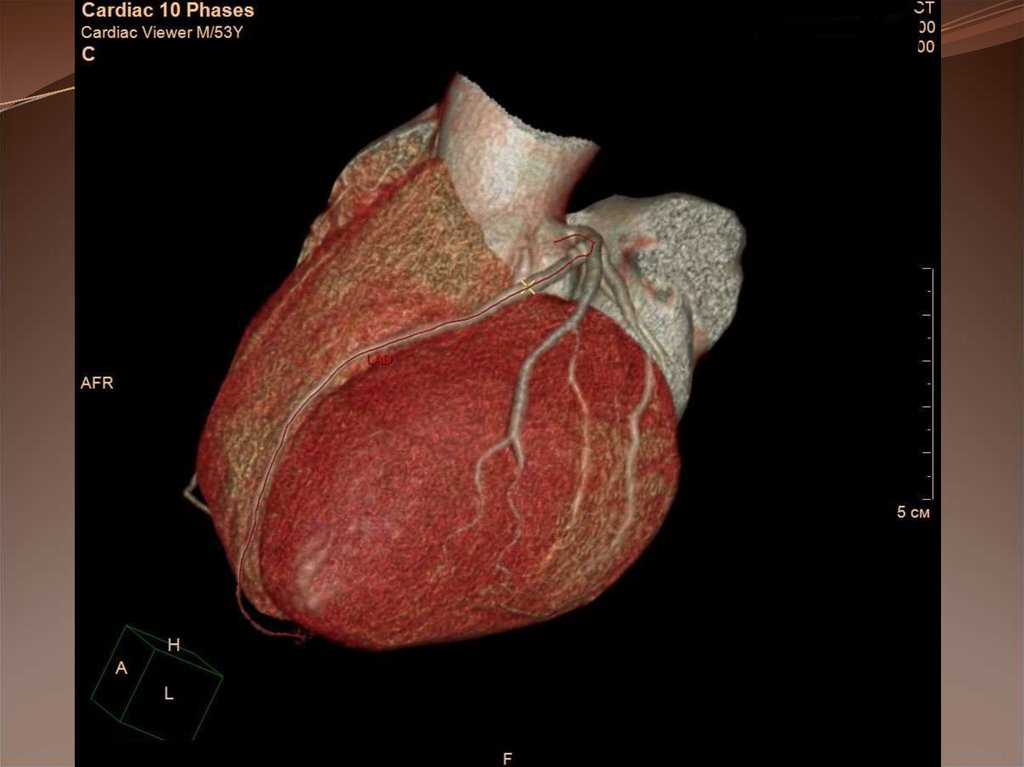

Компьютерная томография коронарных артерий

Компьютерная томография коронарных

артерий.

Методика основана на внутривенном введении

йодсодержащего контрастного препарата с последующим

отслеживанием его прохождения по коронарному руслу при

одновременной записи ЭКГ и последующей математической

обработкой полученных изображений.

Построение трехмерной реконструкции